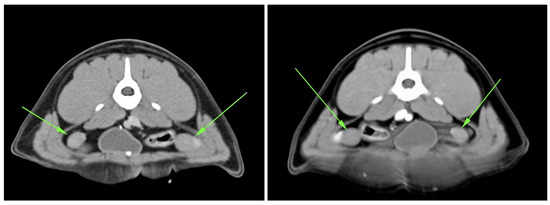

4.1. Clinical Characterization of Brutus